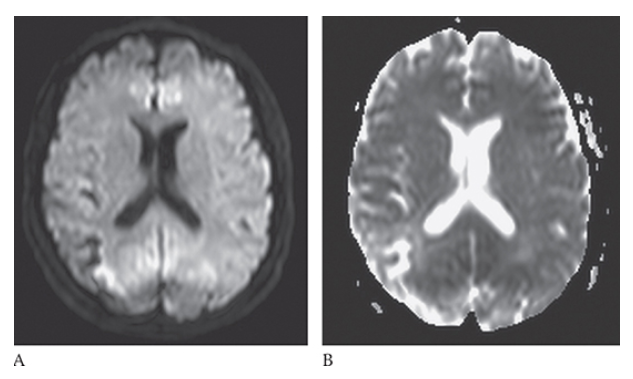

What is A

Ischemic Stroke. The portions of the area are bright on diffusion-weighted imaging but this is also bright on the apparent diffusion coefficient (ADC) map

What is B

Ischemic Stroke. The portions of the area are bright on diffusion-weighted imaging consistent with a subacute infarct.

Ischemic Stroke. In an acute stroke the diffusion will be bright and the ADC map will be dark

Ischemic Stroke. In an acute stroke the diffusion will be bright